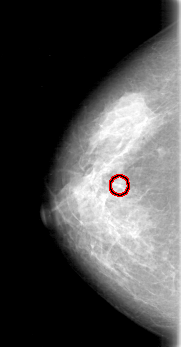

FILE: D_4052_1.RIGHT_CC.OVERLAY

TOTAL_ABNORMALITIES 1

ABNORMALITY 1

LESION_TYPE CALCIFICATION TYPE AMORPHOUS DISTRIBUTION SEGMENTAL

ASSESSMENT 0

SUBTLETY 3

PATHOLOGY BENIGN

TOTAL_OUTLINES 1

BOUNDARY